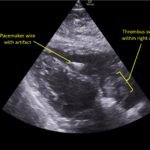

A 78-year-old gentleman presented to the emergency department (ED) for palpitations and dizziness. He had a complicated medical history including atrial fibrillation (AF), recently status post a Watchman procedure, oxygen-dependent chronic obstructive pulmonary disease (COPD), and heart failure with preserved ejection fraction (HFpEF). Point-of-care ultrasound (POCUS) revealed the presence of an intracardiac right atrial thrombus. Computed tomography (CT) angiography confirmed the presence of multiple pulmonary emboli (PE), and extension of the thrombus into the inferior vena cava. Pulmonary emboli are a common complication of thrombus in the right atrium. Management may include anticoagulation, thrombolysis, or thrombectomy. This case highlights that emergency physicians can expedite the diagnosis of intracardiac thrombus by using POCUS. The case presented describes a medically complex patient presenting with symptomatic right intracardiac and inferior vena caval thrombosis complicated by multiple PE. Point-of care ultrasound of the heart and lungs were included in his initial assessment, revealing findings of an intracardiac thrombus, and ruling out multiple other differential diagnoses including pericardial tamponade, pleural effusion, pulmonary edema, and pneumothorax. This finding changed the trajectory of this patient’s evaluation and management, and demonstrates the important role of POCUS in the care of ED patients with undifferentiated cardiopulmonary symptoms.